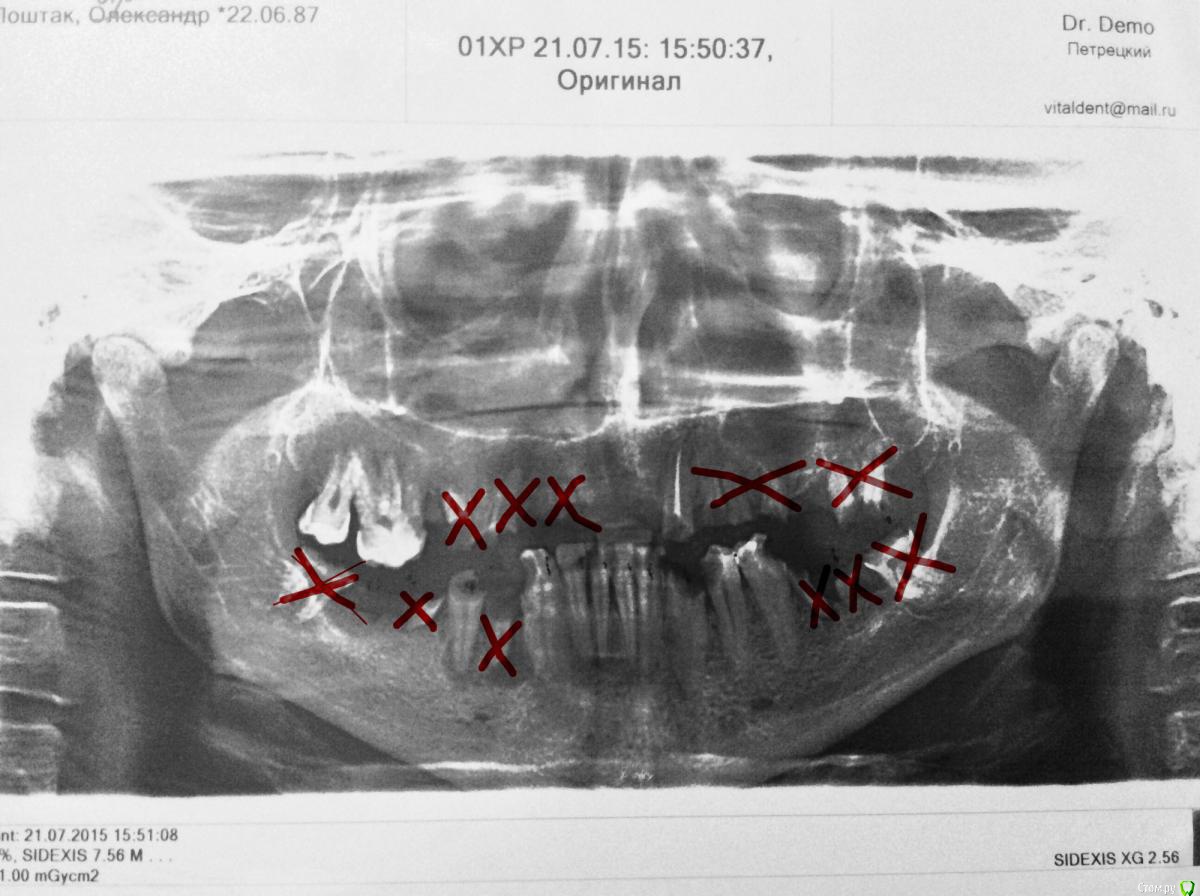

dr.Dre Опубликовано 19 августа, 2016 Поделиться Опубликовано 19 августа, 2016 (изменено) Добрый день коллеги,пациент 28 лет,вот такая ситуация,имплантацию не потянет,ендо уже сделал,раны зажили ,что здесь можно сделать.Можно ли на верх сделать культевые аттачмены? Изменено 19 августа, 2016 пользователем dr.Dre Ссылка на комментарий

4ebstom Опубликовано 19 августа, 2016 Поделиться Опубликовано 19 августа, 2016 Я бы удалил передний зуб и чспп с кламерной фиксацией(если имплантация не рассматривается) 2 Ссылка на комментарий

art700 Опубликовано 19 августа, 2016 Поделиться Опубликовано 19 августа, 2016 По мне такой в такой ситуации удалить зубы и в пспп. Раз такая ситуация в 28 лет. Копить на импланты. Ссылка на комментарий

Fibez Опубликовано 19 августа, 2016 Поделиться Опубликовано 19 августа, 2016 (изменено) что-то мне подсказывает, что эндо зубов + изготовление не шибко надежных конструкции в итоге встанут пациенту дороже чем: 1. низ ПСП на 2-х болатачменах на имплантах2. верх - ПСП Изменено 19 августа, 2016 пользователем Fibez 2 Ссылка на комментарий

Modern Doctor Опубликовано 19 августа, 2016 Поделиться Опубликовано 19 августа, 2016 Я за пспп на верхнюю челюсть и чспп на нижнюю с кламмерной фиксацией на зубы которые ещё могут послужить и мотивировать на имплантацию! В таком возрасте с такими зубами конечно же это беда!!! Ссылка на комментарий

Сева северный Опубликовано 19 августа, 2016 Поделиться Опубликовано 19 августа, 2016 Делаю такие протезы с целью временной реабилитации перед имплантацией. Сохранение корней зубов( с культевыми вкладки с атачменами) когда уменьшается длина зуба ... рычаг... дает возможность сохранить обьем вокруг них для последующей установки имплантантов .Под таким сьемником, можно провести санацию других областей( например синус лифтинг) .Культевые атачменты ставятся как правило на фронтальную группу зубов, и как показала практика при наличие опоры в дистальном отделе (например телескоп)выживаемость протеза резко повышается. Так же отлично выручают при десневой улыбке. Ссылка на комментарий

Doc.IQ Опубликовано 19 августа, 2016 Поделиться Опубликовано 19 августа, 2016 Конечно же сдесь решать вам..если так хочется оставить эти зубки,то как вариант сделать псп на внутрикорневых атачментах,но никак не телескопах..границы протеза вывести как на истинном пспп и в будущем,когда эти зубы удалятся,перевести этот протез в пспп посредством перебазировки в п/рта..Р.s. Незабудьте про усиление протеза(отлить индивид.сетку либо дугу,в которой будет находится ответная часть внутрикорневых атачментов) Ссылка на комментарий